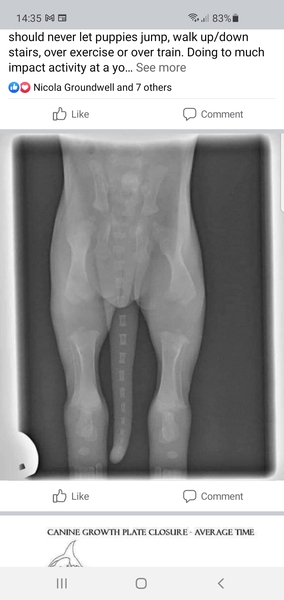

Please be careful with her jumping around, as this picture shows her bones have yet to lock in.

I'm not sure how to stop her ? We are lifting her up and down stairs, on and off sofa and absolutely trying to discourage jumping up but this is while tearing round the room in high speed puppy zoomies 🤷‍♀️